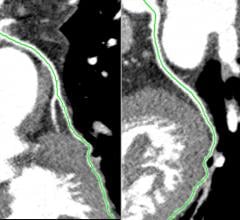

Results from the PROMISE clinical trial confirmed what many cardiologists and radiologists have long suspected to be true: Coronary computed tomographic angiography (coronary CTA) is extraordinarily effective in accurately diagnosing patients with low to moderate chest pain.